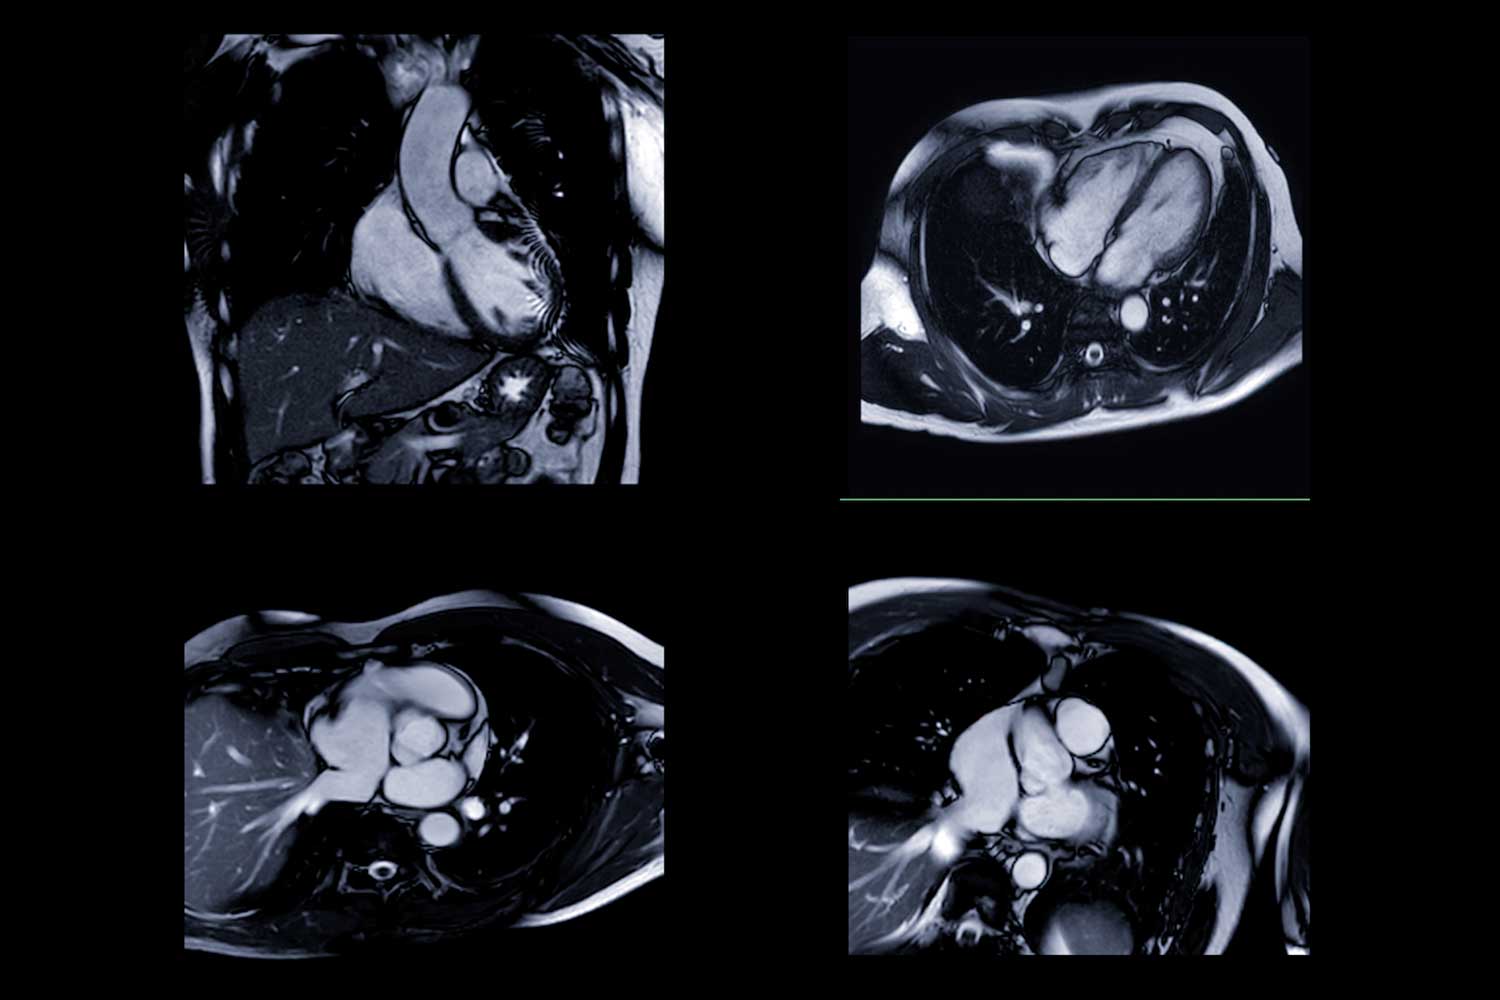

A heart MRI is an imaging test that uses strong magnets and radio waves to create detailed images of your heart muscle, chambers, valves, and nearby blood vessels. Unlike X-rays or CT scans, MRI does not use ionizing radiation, making it a safe option for many patients.

Cardiac MRI gives doctors a clear view of how well your heart works and can show subtle changes that other tests might miss.

- Powerful magnets and radio waves create images of your heart from different angles.